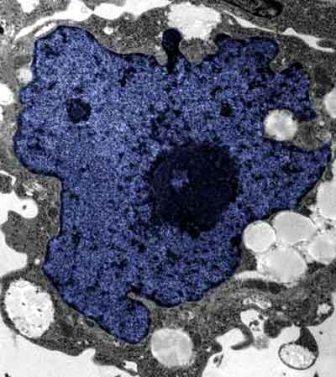

在成人體內(nèi)及胚胎內(nèi)發(fā)現(xiàn)的干細胞屬于主細胞,能發(fā)育成各種各樣的組織,可作為人體“修補工具箱”,取代死去及腐壞細胞組織。此前,最可行的干細胞為胚胎干細胞,但它的使用一直受到爭議,因為要在胚胎抽取干細胞會令胚胎死亡,有人認為這樣是變相奪走一條生命。

2007年,日本京都大學(xué)教授山中伸彌為首的科研小組證明,利用病毒倒撥普通皮膚細胞的“生理時鐘”,可把它們變成像胚胎干細胞那樣具備“變身”能力的細胞。但利用病毒把基因輸入細胞,有可能導(dǎo)致癌癥。這即是說使用這些細胞的風險很大。

來自英國和加拿大的兩組研究員所用的新方法不必使用病毒。這項新突破暗示科學(xué)家現(xiàn)在能更認真地看待在醫(yī)學(xué)中利用皮膚干細胞(即誘導(dǎo)多功能干細胞,俗稱“iPs”細胞)的前景。

這些細胞只要配以適當?shù)幕瘜W(xué)品和蛋白質(zhì),就能轉(zhuǎn)化成腦神經(jīng)元、制造胰島素的胰腺細胞、骨或軟骨、心臟肌肉,或其它多種組織。這些細胞利用病人皮膚來培育,更暗示它們不會被人體排斥。